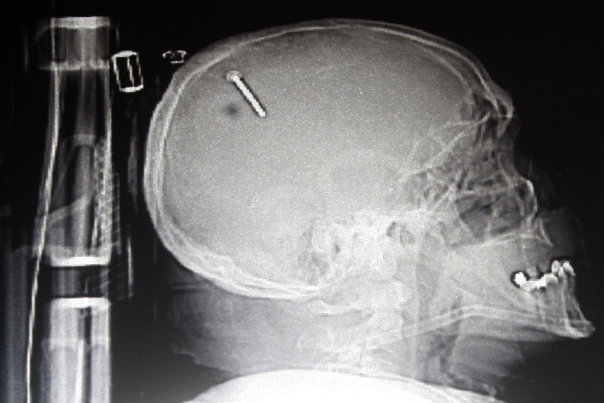

I TO JE MOGUĆE

Nevjerojatne ozljede sa sretnim ishodom

FOTO GALERIJA - Da neki ljudi imaju više sreće nego pameti pokazuju sljedeće rentgenske snimke

2. Snimka pokazuje čavao u glavi Georgea Chandlera iz savezne države Kansas. Chandler i prijatelj radili su na projektu kada je pištolj za ispaljivanjE čavala iznenada opalio. Chandler je kasnije izjavio kako nije znao gdje je metak završio ali je osjetio lagani ubod na vrhu glave.